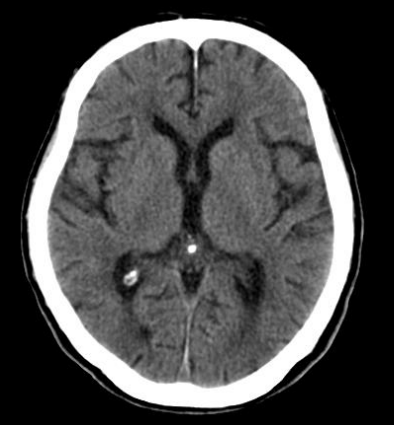

A tomografia de crânio é um exame não invasivo de diagnóstico por imagem que possibilita o estudo do encéfalo, ossos da face e mandíbula. Os equipamentos de tomografia fazem diversos cortes (imagens), cada “corte” refere-se a uma imagem individual e corresponde a uma “fina fatia” do segmento do crânio a ser analisada. Assim sendo, é possível recompor por meio de técnicas todos os segmentos obtidos, produzindo uma série de imagens finais que serão analisadas pelo médico radiologista, com muita qualidade e precisão. Em algumas situações, é solicitado o uso de contraste iodado – via endovenosa-, para uma visualização mais detalhada da área desejada e estruturas vasculares.

É um excelente método de imagem para observar fraturas e lesões hemorrágicas.